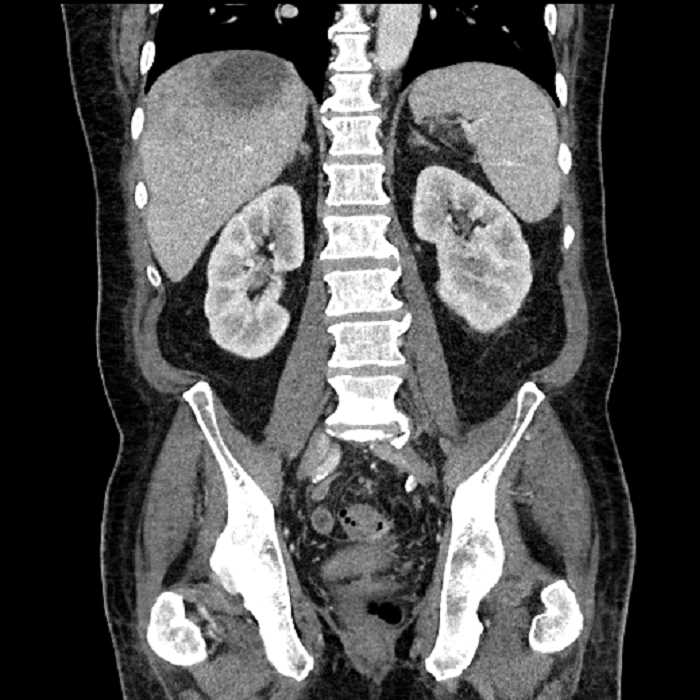

Age: 63

Sex: Male

Indication: Abdominal pain

• High grade stenosis of the left common iliac artery, with the left internal and external iliac arteries remaining patent

• Ankylosis of both sacroiliac joints

High grade stenosis of the left common iliac artery. The left external and internal iliac arteries are patent.

Hepatic abscess showing the double target sign with low density internally surrounded by a thin inner enhancing rim (red arrow) and ill-defined outer low density rim (yellow arrow). Blue arrow indicates an internal septation. Red arrows: additional smaller subcapsular abscesses. Red arrow: focal contained perforation associated with diverticulitis.